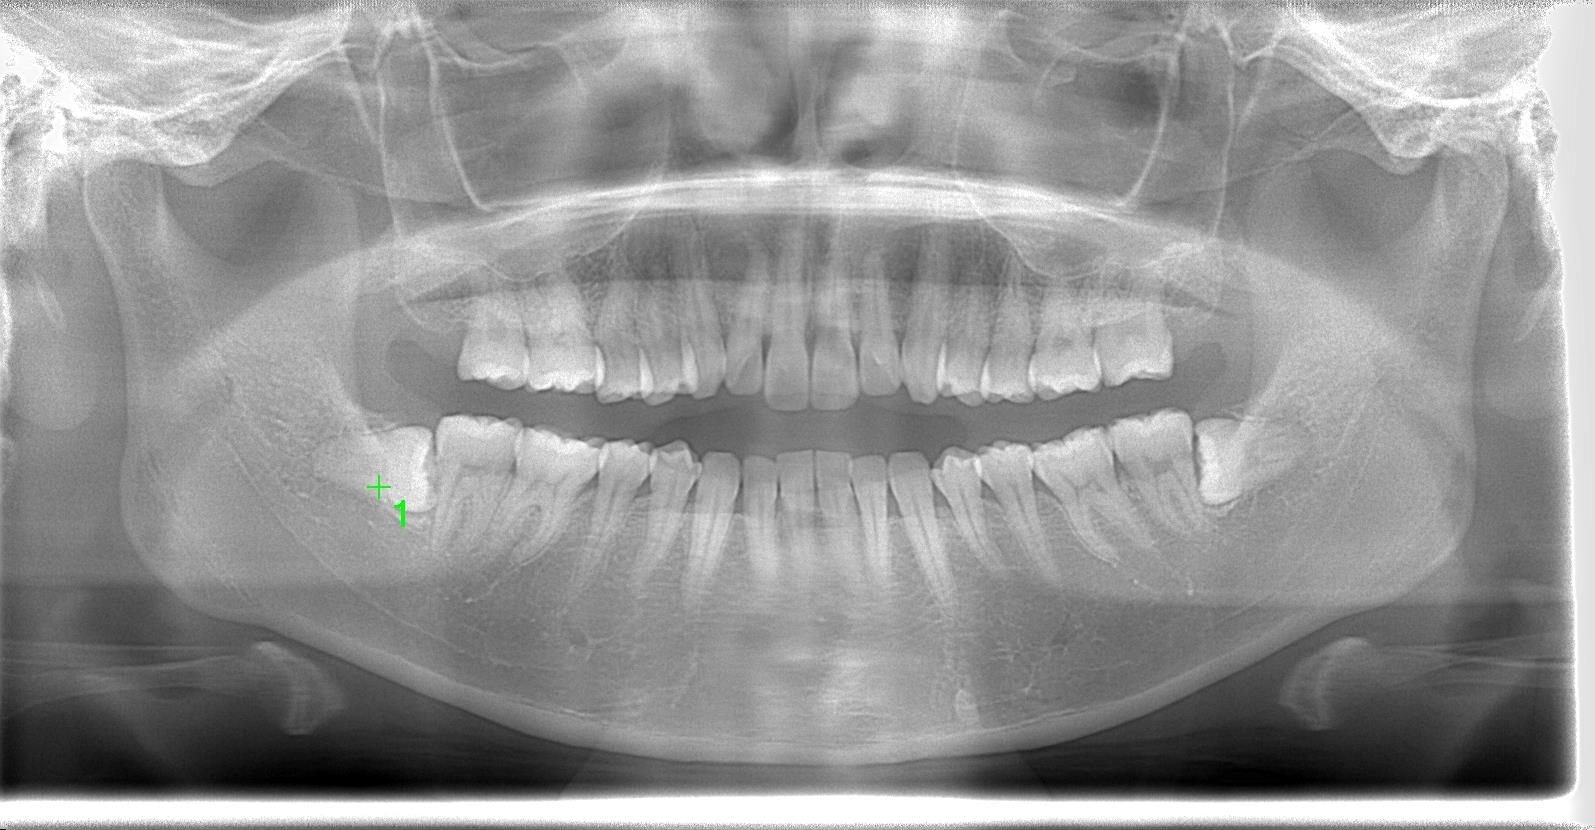

30代前半女性、8埋伏歯の抜歯の難症例

レントゲン写真の状態を御覧ください。

術前

部位:右下8番骨性完全埋伏歯

部位:左下8番骨性完全埋伏歯